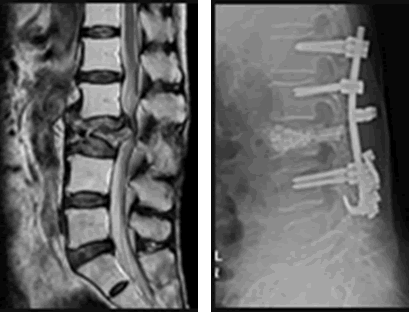

破裂骨折では、通常はレントゲンとMRIを撮影します。脊柱の破裂骨折で、圧壊が進行したり、神経症状があったりする場合、手術による固定を行います。

脊椎の破裂骨折が起きたとき、受傷直後に緊急的に固定術をすることが多いです。

固定術をした場合、脊柱に変形を残すもの(11級7号)となる確率は高いです。